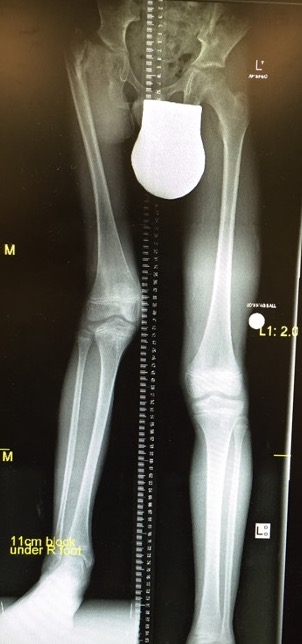

4. LLD

2. Equalise LLD

- lengthen femur or

- shorten / epiphysiodesis other femur

Note:

- if lengthen femur need to watch knee doesn't dislocate

- ACL deficient

- may have to bridge knee with external fixator

Foot above contralateral knee

- knee fusion + symes

- essentially AKA

Foot below contralateral knee

- rotate then fuse knee / Van Ness Rotational Osteotomy

- ankle acts as knee joint / essentially BKA